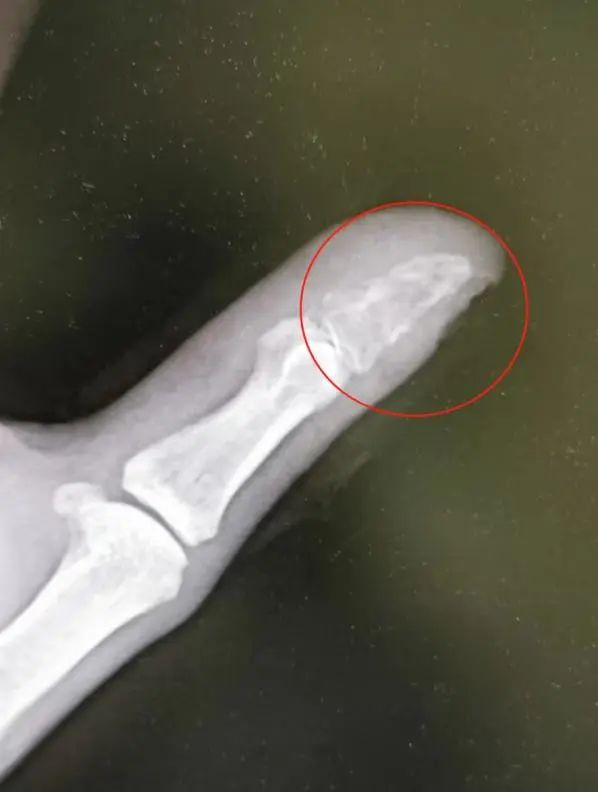

经检查,蒋先生伤口感染严重,拍片显示拇指末节指骨也被细菌侵蚀“吃空”,存在截指的风险。

目前,蒋先生的感染情况已经得到了控制,医生尽力保住了他的拇指,后期将进行植骨手术治疗。